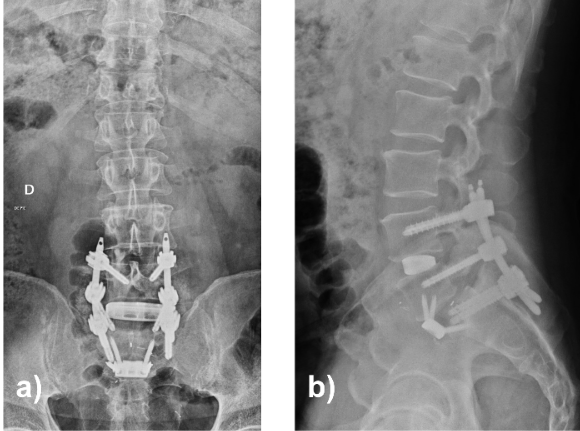

Early post-operative improvement was followed by new persistent left-sided radiculopathy. CT demonstrated a subfascial fluid collection, and re-exploration was performed. Hematic fluid was evacuated, and a mobile osseous fragment at the proximal S1 dome and L5 axilla was identified, causing dynamic root compression. The fragment was resected, and decompression extended. The construct remained stable. The patient was subsequently referred to endocrinology, where treatment for osteoporosis was initiated. Over subsequent follow-up, the patient demonstrated progressive reduction in radicular and axial pain with functional recovery. At final follow-up, the patient remained clinically stable without recurrence of symptoms, with imaging confirming progressive fusion and consolidation of the S1 fracture (Fig. 6).

Figure 6: Lumbosacral radiographs 8 months postoperatively in anteroposterior (a) and lateral (b) projections.